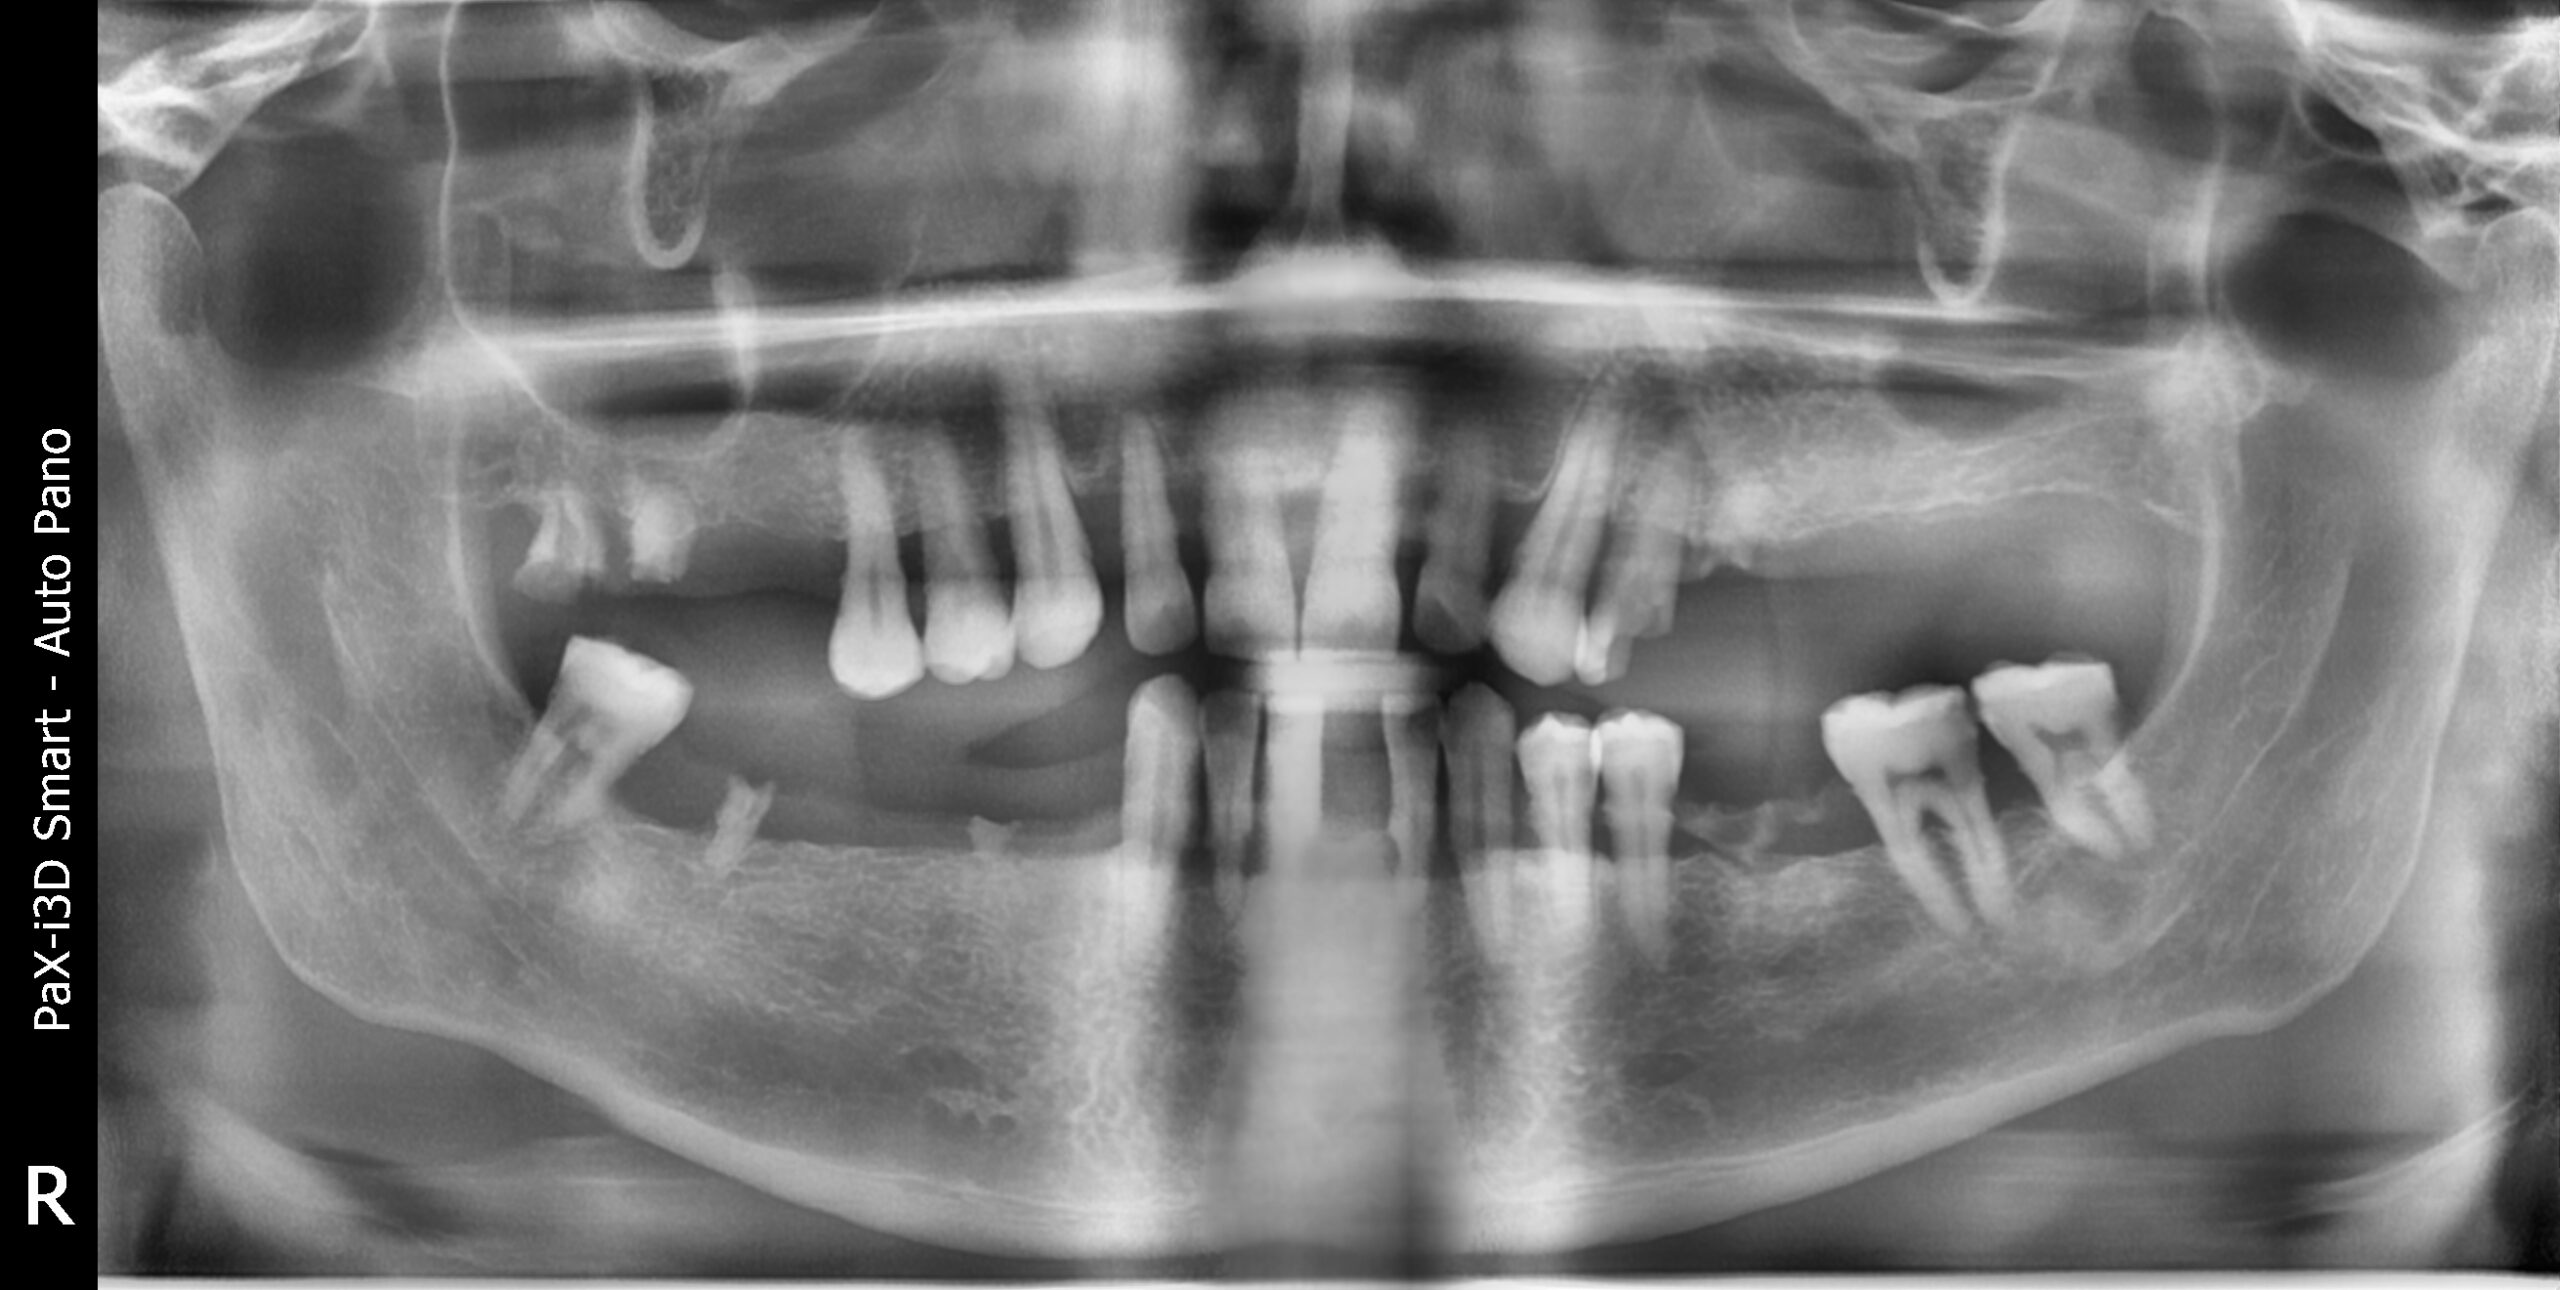

In questo caso clinico abbiamo trattato un paziente, uomo di 63 anni, con gravi problemi parodontali e con la mancanza di numerosi denti, altri erano molto mobili e non potevano essere recuperati. Il paziente desiderava risolvere il problema che si protraeva da diversi anni. Non era soddisfatto del suo sorriso, non riusciva a mangiare correttamente e si sentiva molto a disagio.

Insieme al paziente abbiamo deciso che la soluzione migliore fosse una riabilitazione totale delle due arcate con la rimozione dei denti residui e l’inserimento di 4 impianti nell’arcata superiore e 4 impianti nell’arcata inferiore, sui quali sarebbero state poi avvitate le protesi fisse (All on four).